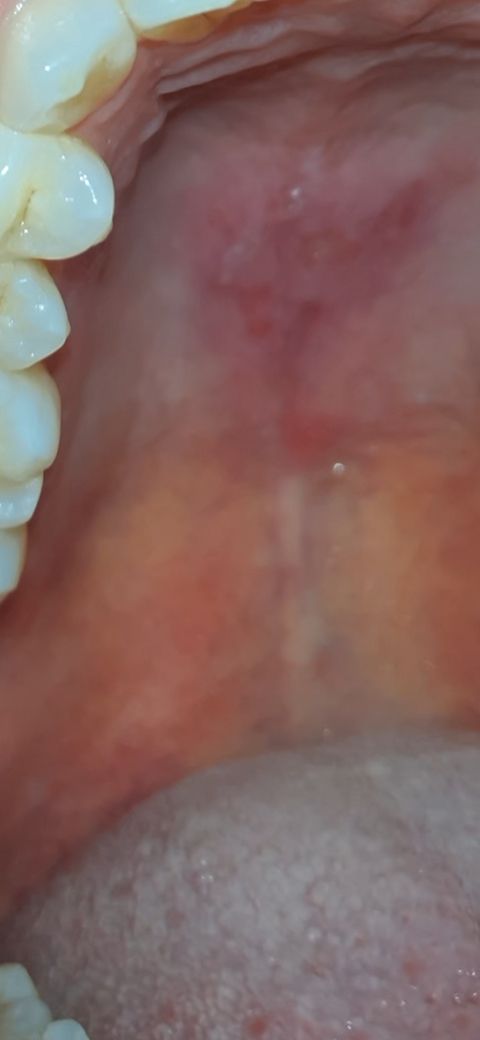

입안 천장이 쓰라리는데 구내염 일까요?

엊그제 입 천장이 엠보싱 처럼 올록볼록 해지더니 헐렀는지 따가워서요

잇몸에 구내염 혹은 궤양 등이 생긴 것으로 보입니다. 오라메디와 같은 약을 사서 면봉으로 발라주시면 됩니다.

온도변화가 심하거나 날카로운 음식을 먹는다면 구강점막에 손상이 가해질수 있습니다.

이런 손상은 대부분 시간이 지나면서 치유가 되기때문에 해당부위를 자극하지 않는것이 좋습니다.